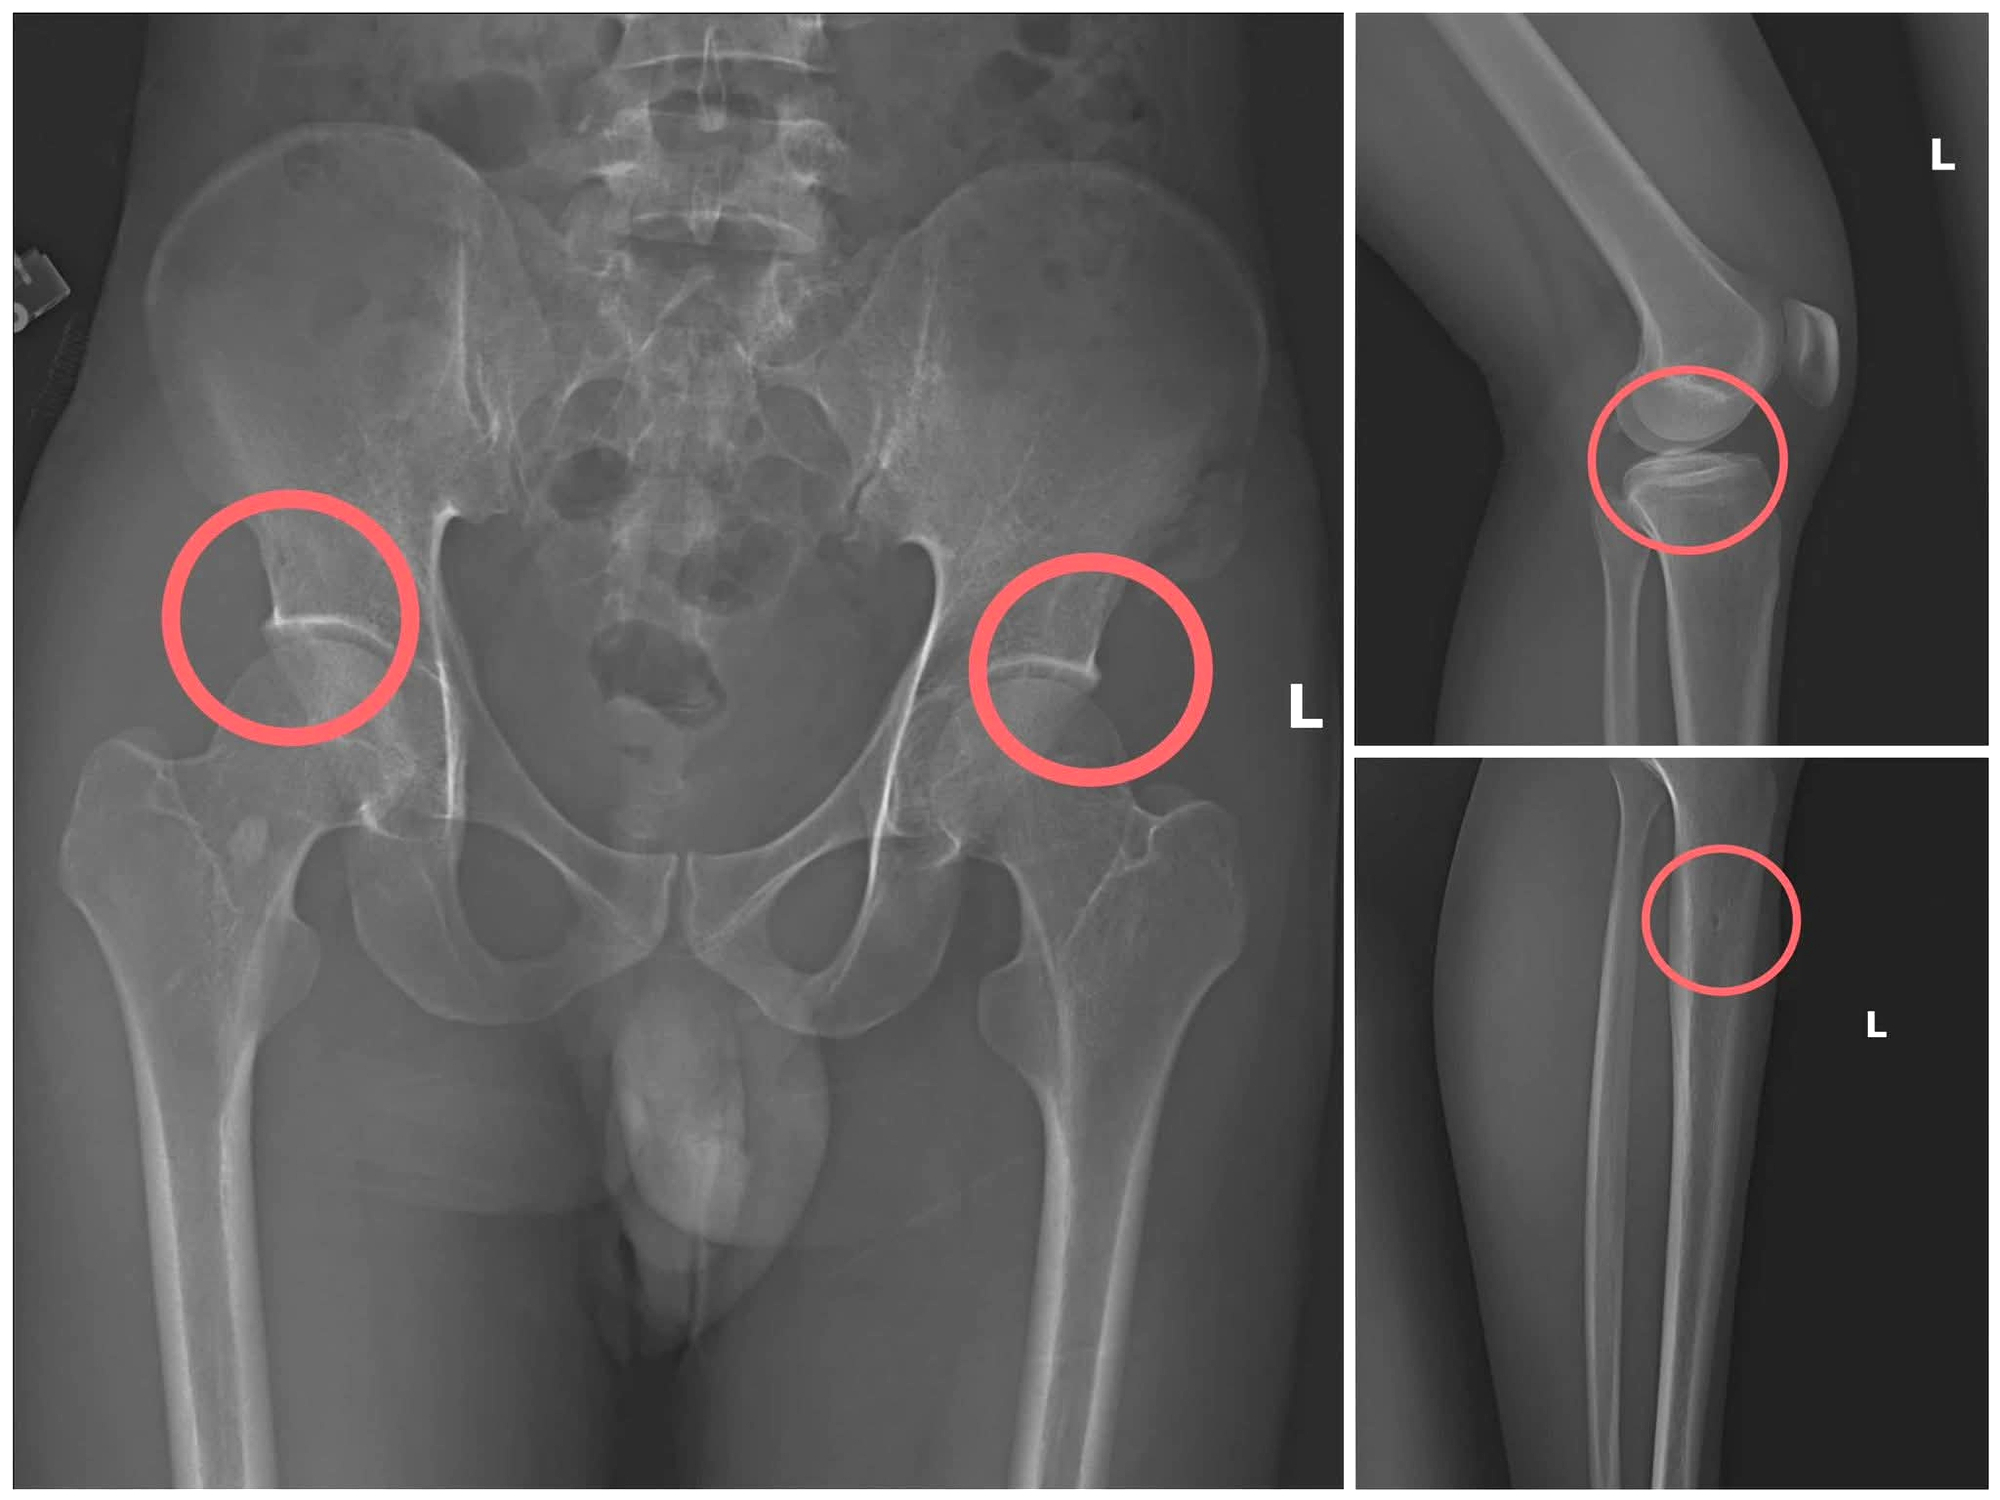

Bản phim chụp XQuang một số tổn thương do đối tượng tạo ra.

Đáng chú ý, Châu trực tiếp thực hiện hành vi tiêm thuốc mê, rồi dùng kim tiêm, búa, đinh để tác động vào xương người mua bảo hiểm, tạo nên các vết nứt, vỡ xương tương tự tai nạn thật.

Lợi dụng thời gian dài công tác trong ngành y và am hiểu sâu cấu tạo xương - khớp, cũng như cơ chế chi trả bảo hiểm đối với các thương tích gãy xương giá trị cao, Châu đã dựng lên một quy trình trục lợi bài bản, từ việc vận động mua bảo hiểm, tổ chức gây thương tích, đến hợp thức hóa hồ sơ bệnh án để chiếm đoạt tiền của các công ty bảo hiểm.

Theo đánh giá của Giám đốc Công an tỉnh Phú Thọ Nguyễn Minh Tuấn, thủ đoạn này vừa tàn nhẫn, vô nhân tính, coi thường sức khỏe, tính mạng của người tham gia bảo hiểm, vừa được tính toán kỹ để gây thương tích đúng vị trí có mức chi trả cao, khiến các công ty bảo hiểm khó phát hiện dấu hiệu gian dối.